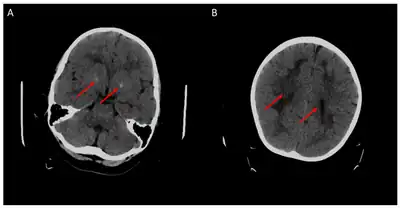

a)Extensive white matter disease b) atrophy of frontal hemispheres and cerebellum -

Cerebral CT-scan at 4 years old. Red arrows show brain calcifications (A) and diffuse white matter abnormalities (B). From Mafi et al., 2020[15]